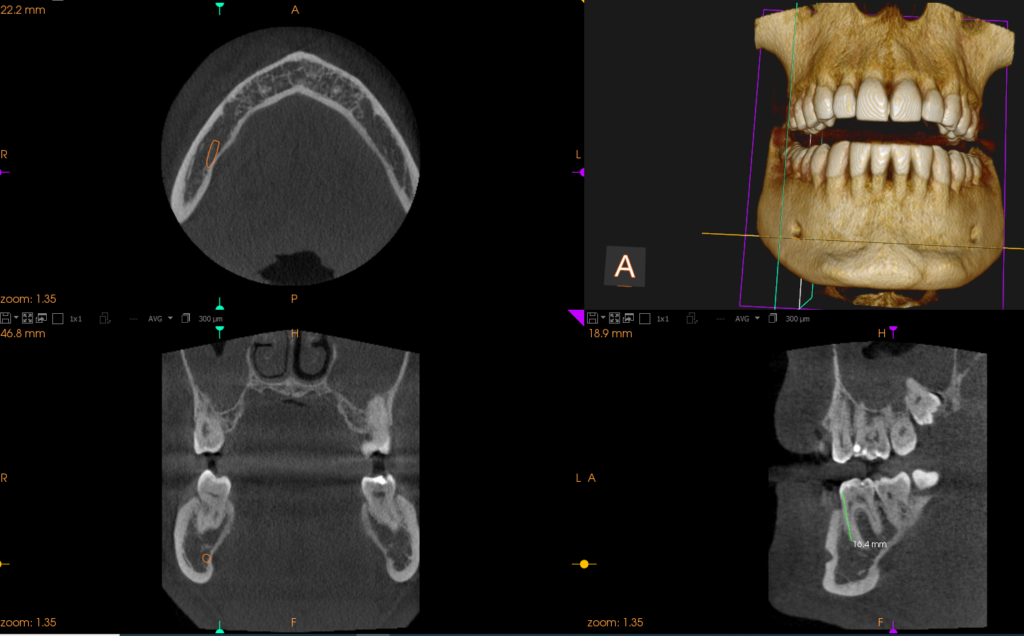

L’ implantologia computer guidata è una rivoluzionaria ed innovativa procedura che permette di progettare al computer, tramite l’utilizzo di precisi software, l’intervento di inserimento degli impianti dentali nelle ossa. Il tutto è possibile tramite un protocollo digitale che prevede prima l’acquisizione di immagini radiografiche 3D proveniente dall’esame CBCT (tac dentale) sovrapposte alle immagini 3D provenienti dalla scansione intraorale della bocca del paziente. Il progetto implantare così eseguito dal medico al pc viene poi trasferito nella bocca del paziente tramite delle dime chirurgiche che fungono da guida per il chirurgo durante l’intervento. Questa procedura rende l’intervento meno invasivo, a volte senza rendere necessari punti di sutura, utilizzando una precisione computerizzata.